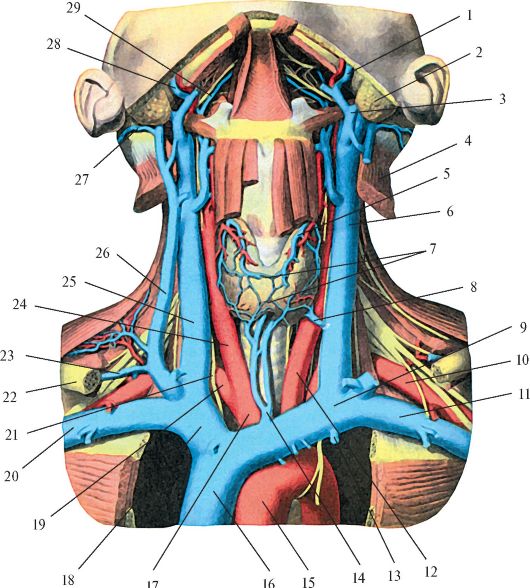

Анатомия внутренней яремной вены: КТ изображения